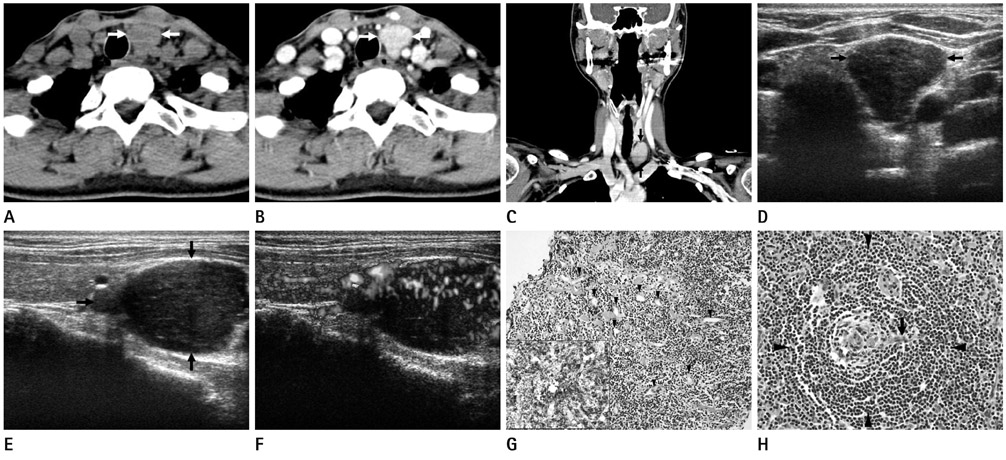

Castleman Disease of Hyaline Vascular Type in the Infrathyroidal Region: A Masquerader of Parathyroid Adenoma

- Castleman disease of the infrathyroidal region is extremely rare. We report both CT and sonographic findings of a case of infrathyroidal paratracheal Castleman disease of hyaline vascular type, which masquerades parathyroid adenoma, in a 48-year-old woman. We further provide its histological findings at sonographically guided core-needle biopsy (US-CNB) and excisional biopsy. The lesion was ovoid with homogeneous intense enhancement on contrast-enhanced CT (CECT), and was homogeneous, markedly hypoechoic, and hypervascular on ultrasonography (US). Histological findings of the specimen obtained by US-CNB suggested lymphoproliferative lesion, and thus was inconclusive; those obtained by excisional biopsy were characteristics of Castleman disease of hyaline vascular type. Hyaline vascular type Castleman's disease should be included in the differential diagnosis of a mass of the infrathyroidal region with homogeneous intense enhancement on CECT, as well as with marked hypoechogenicity and hypervascularity on US. US-CNB may be of limited value in the histological diagnosis of this entity.